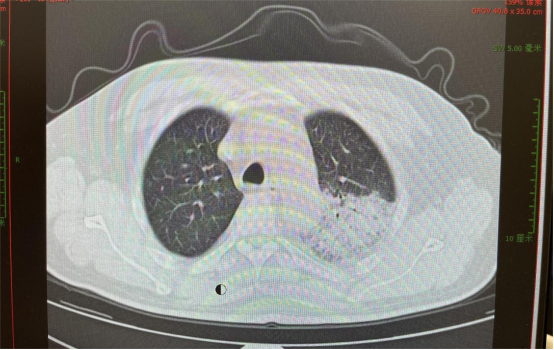

image.png 入院10天后胸部CT显示病灶部分吸收